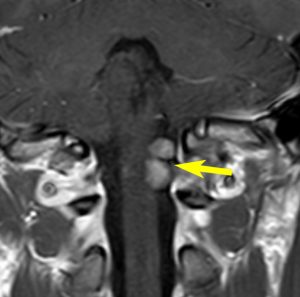

症例:小脳延髄角槽のもの,頸静脈孔へ少し入るもの

30歳くらいの女性に発生した無症状のものです。矢印のように拡大した頸静脈孔へ少し入っています。定位照射でもよかったかもしれませんが,若い女性なので手術しました。

脳槽部迷走神経根から発生したと考えて,外側後頭下開頭で摘出しましたが,予想外に延髄に近い部分の迷走神経から剥がせず,ほんの少し神経根の上に残しました。術後10年経ちますが腫瘍再燃はありません。聴神経腫瘍で顔面神経の上に薄く腫瘍を残すのと同じ考え方です。